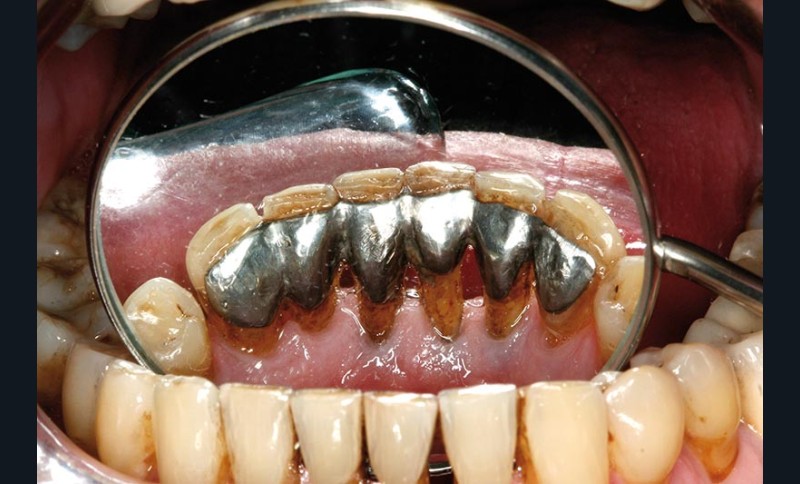

Une patiente présente un proglissement mandibulaire aboutissant à une inversion d’occlusion au niveau des incisives (fig. 2).

Au-delà du préjudice esthétique, il induit des forces importantes en direction vestibulaire sur les incisives mandibulaires. Ces incisives présentent une légère mobilité. La radio rétro-alvéolaire montre un élargissement desmodontal et une perte osseuse verticale sans cratérisation ni inflammation (fig. 3).